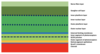

What are all the layers in the retina?

Inner at top

Outer at bottom (photoreceptors where transduction occurs)

What is the imaging of this picture?

Optical coherence tomography

What is the foveal dip?

- Where light entering the eye causes the sharpest image

- Increase in visual acuity

- Increase in determination of colour

-

Fovea appears slightly darker as it is thinnest here

- Choroid is most visible

- Hence, light can get straight to photoreceptors